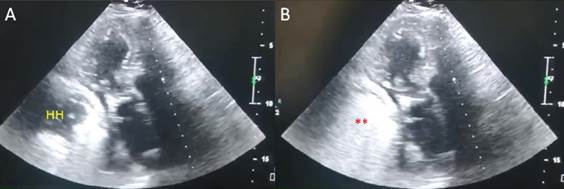

Luego, con este planteo se realiza un nuevo ecocardiograma Doppler con el fin de contar con una técnica de mayor accesibilidad para un eventual seguimiento cardiovascular. En este se constata una regular ventana ultrasónica y se evidencia una masa retroauricular en íntimo contacto con la aurícula izquierda y sobre pared inferolateral del ventrículo izquierdo de difícil caracterización (figura 2A). Contando con la información de la resonancia se completa el estudio ecocardiográfico y se le pide a la paciente que ingiera una bebida carbonatada en decúbito supino (en este caso, agua con gas, a modo de “contraste”). Se visualiza el pasaje de las microburbujas al interior de la masa (en este caso, el estómago), lo que permite confirmar el diagnóstico ecocardiográfico de hernia hiatal (figura 2B). Dados estos hallazgos en los estudios de multimodalidad de imagen cardiovascular, es enviada por su médico tratante a valoración por equipo de gastroenterología y cirugía para definir directivas del tratamiento a seguir.

Figura 2: Ecocardiograma doppler en vista apical eje largo. A) Se observa una masa anecoica en su interior que corresponde a una hernia hiatal (HH) en el sector posterior de la aurícula izquierda y pared inferolateral del ventrículo izquierdo. B) Luego de que la paciente ingiere una bebida carbonatada (agua con gas) se observa como las burbujas pasan al interior del estómago (**) lo que confirma la presencia de hernia hiatal mediante ecocardiografía.